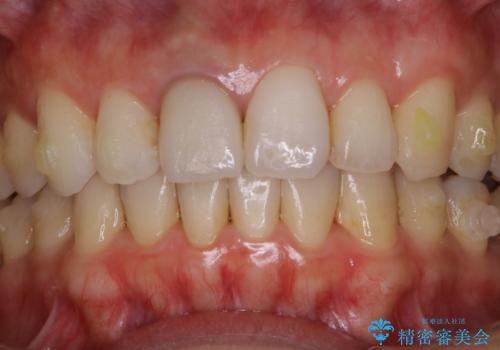

- インビザラインでのマウスピース矯正中にステインや着色を取りたいとのことでした。

PMTC60分コースを行いました。

PMTC(保険外治療)は、毎日の歯磨きで落としきれない汚れや、コーヒ、紅茶・タバコのヤニなどの着色も除去します。目には見えない歯と歯の間・歯肉の境目・インビザライン中はアタッチメント周囲などに残っているプラーク(歯垢)もしっかり取り除きます。PMTCでは専門的な機械や材料を使用して、徹底的に汚れを除去するため、虫歯・歯周病・口臭予防などにつながります。

またPMTCを行うことで、ご自身本来の歯の色になり自然な明るさになります。